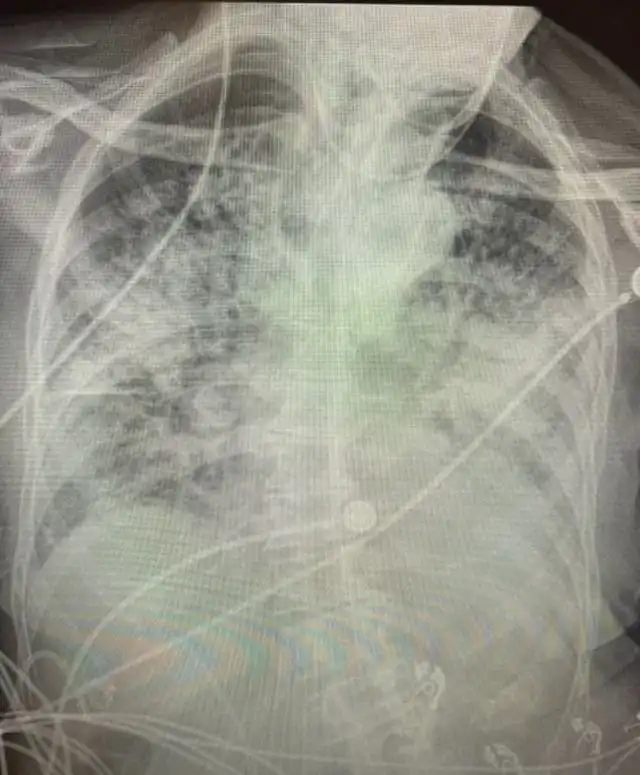

А это - лёгкие человека, переболевшего COVID-19

Как рассказала доктор изданию NewsNationNow, белая "паутина" на снимке - это оставшиеся рубцы на лёгких. Невооруженным взглядом видно, что легкие после коронавируса выглядят намного хуже, чем легкие курильщиков. По словам врача, после COVID-19 отдышка сохраняется на долгое время, а также не исчезает риск появления тромбов и возникновения пневмоторакса.

Помимо этого, Бриттани Банкхед-Кендалл отметила, что даже если человеку кажется, что с его лёгкими всё в нормально, на рентгене может оказаться совершенно иная картина. Иногда проблемы остаются даже у тех, кто уже давно выздоровел, и они могут сохраниться на всю оставшуюся жизнь.